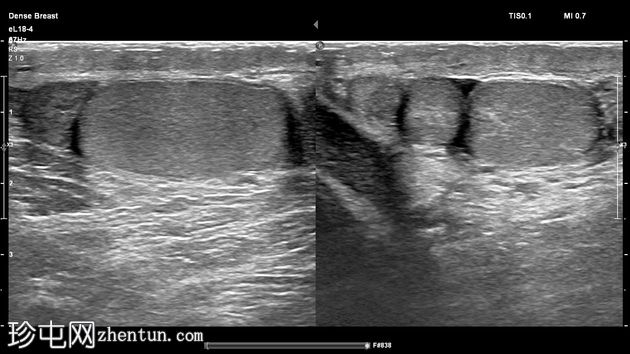

左侧阴囊内可见两个相邻但彼此分离的小睾丸,头侧体积分别为1毫升和3.5毫升,共用一个附睾。

两个睾丸回声和血流均正常,内部未见病变,但患侧可见少量鞘膜积液。